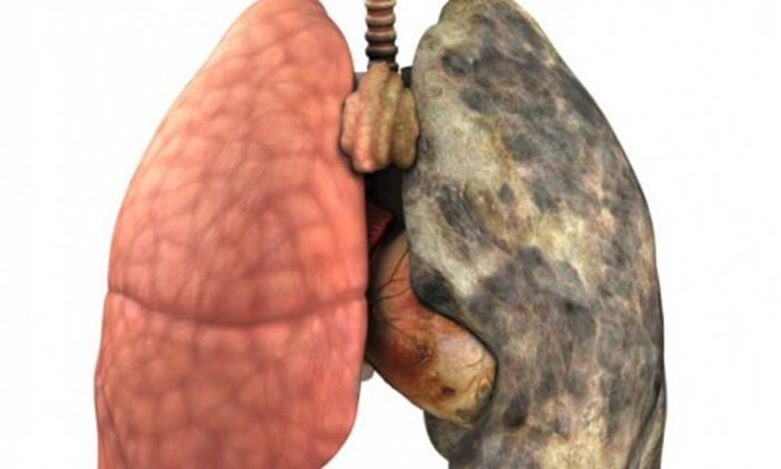

Səbəbləri, risk faktorları

Siqaret və hava çirklənməsi əsas səbəblərdir. Əsrin ilk dekadalarına qədər ağciyər xərçəngi az rast gəlinirdi, lakin 30-cu illərdən sonra siqaretin geniş istifadəsi ilə əlaqədar ağciyər xərçəngi sürətlə artdı və hazırda ikinci yerdə durur (kişilərdə prostat xərçəngindən, qadınlarda süd vəzi xərçəngindən sonra)

Ağciyərin bəzi xəstəlikləri xərçəng riskini artıra bilir. Bunlara vərəmi, xroniki pnevmoniyanı, çapığı və azbestozu aid etmək olar.